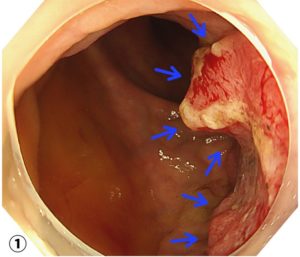

当院の大腸内視鏡で見つかった進行直腸癌